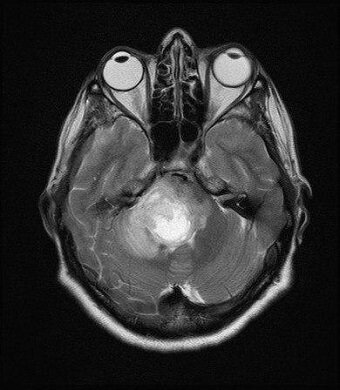

«Изначально мы заподозрили инсульт. Однако выяснилось, что в начале октября женщина перенесла ОРВИ с высокой температурой, кашлем и катаральными явлениями, после чего и возникли симптомы, характерные для инсульта. Коллегиально мы провели пациентке углубленную нейровизуализацию. Мультидисциплинарный подход в диагностическом поиске позволил выявить абсцесс мозга редкой локализации — в стволе головного мозга», — рассказала заведующая первичным сосудистым отделением больницы Татьяна Ануфриева.

В результате пациентка была маршрутизирована в МОНИКИ имени М.Ф. Владимирского в нейрохирургическое отделение третьего уровня для оперативного лечения. Женщина уже успешно прооперирована и в настоящее время проходит первый этап реабилитации.